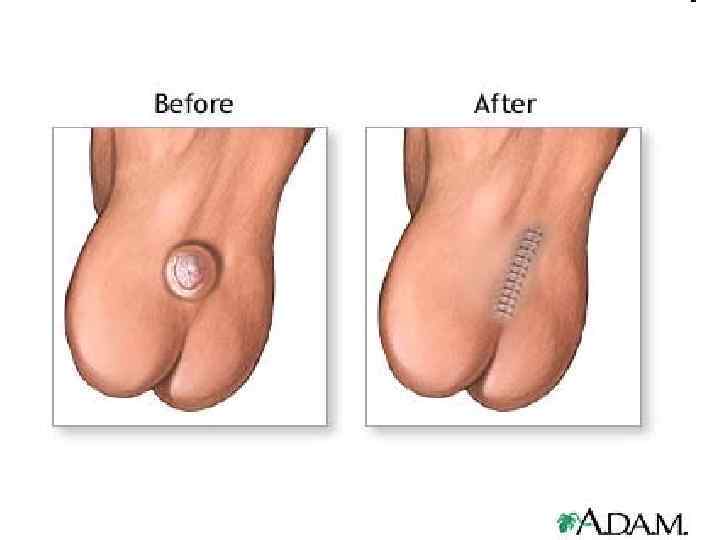

120

121